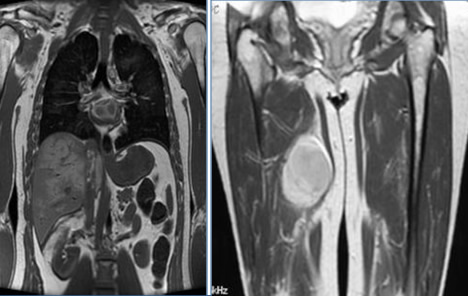

MRI

“MRI has excellent contrast, spatial and temporal resolution; however, there are many image acquisition variables involved in MRI, which greatly impact image quality, lesion conspicuity and measurement. The availability of MRI is variable globally. Chest MRI not recommended”

• Measurements are possible on isotropic reconstructions and non-axial MRI planes:

• sagittal

• coronal

• (oblique)

Also here the key point is consistency. Always measure in the same plane.